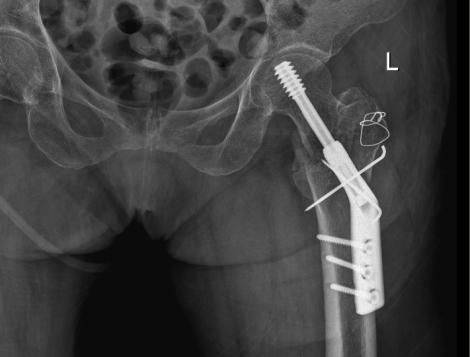

△右側(R)是賴婆婆3年前跌斷股骨術後,左側是本次手術術後。

吳志斌主任通過CT+三維重建先行拟定詳細手術方案,提前做了精心準備。根據患者的年齡特征,爲其選擇最佳的半髋置換方案,并采用雙動人工股骨頭,提高活動範圍,減少髋臼磨損。

10月20日,老人家被送進了手術室行左側人工股骨頭置換術。吳主任根據方案按部就班地實施手術,娴熟地完成每一個手術步驟,精心地把控每一個細節,确保髋部良好的活動性和穩定性,以及雙下肢等長。整個手術過程非常流暢、一氣呵成。術中患者各項生命體征平穩,術後平安返回病房。